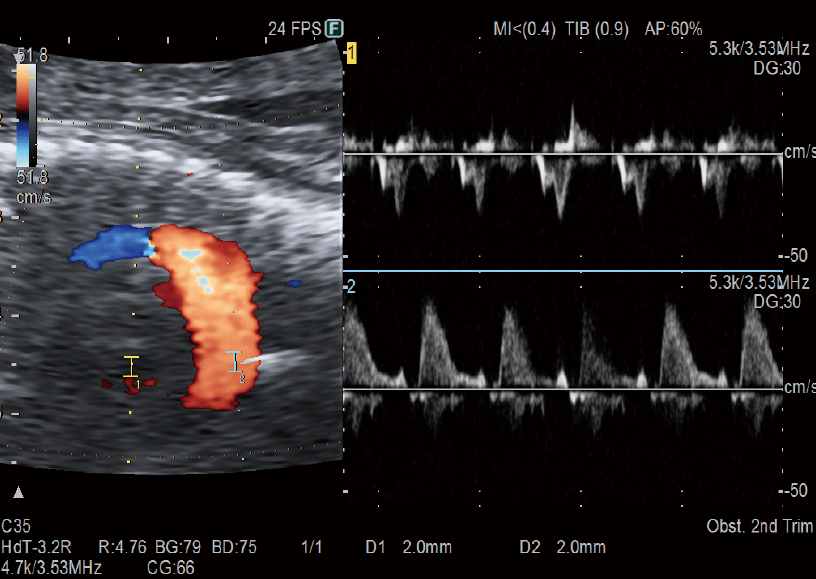

Enables the observation of Doppler waveforms from two different locations during the same heartbeat. The rhythm of atrial and ventricular systole can be evaluated more efficiently than single Doppler methods.